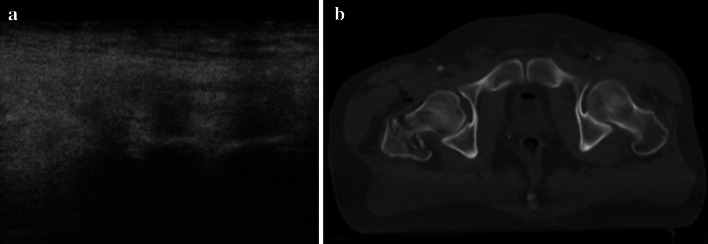

Fig. 2.

a US shows the normal aspect of pubic symphysis and b CT demonstrates the lack of diastasis of the pubic branches